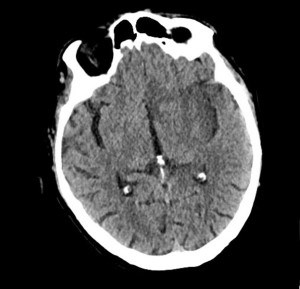

Diagnosis of HSV encephalitis can be through lumbar puncture, which most often shows pleocytosis of cerebral spinal fluid with lymphocytic predominance and elevated protein. Brain CT (Image 1) or MRI can also be used as a diagnostic tool displaying temporal lobe abnormalities.7

Image 1. CT revealing signs of CNS dysfunction